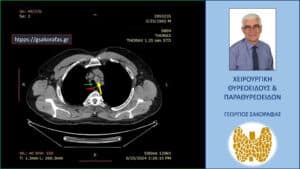

Για την αξιολόγηση του βάθους κατάδυσης του θυρεοειδούς στο μεσοθωράκιο ο ασθενής υποβλήθηκε σε αξονική τομογραφία όπου ο αριστερός λοβός απεικονίζεται σε θέση κατάδυσης μεταξύ της έκφυσης της αριστερής κοινής καρωτίδας και της ανωνύμου αρτηρίας φτάνοντας εγγύς του άνω ορίου του αορτικού τόξου. Ασθενής ευθυρεοειδικός.

Απεικόνιση στην αξονική τομογραφία σε κατά μέτωπο διατομή (σε άλλο επίπεδο) όπου ο καταδυόμενος αριστερός λοβός του θυρεοειδούς (κίτρινο βέλος) φαίνεται να βρίσκεται μεταξύ της έκφυσης της αριστερής κοινής καρωτίδας και της ανωνύμου αρτηρίας από το αορτικό τόξο (ΑΟ).